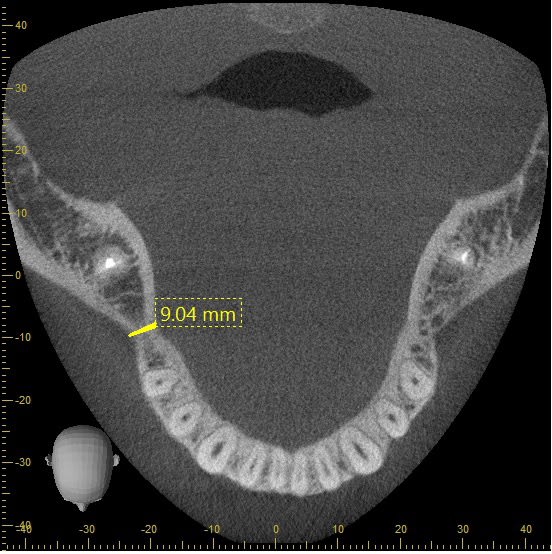

déjà, juste à vue de nez, les 9 mm indiqués sur ta première image ne sont certainement pas disponibles sur ta partie utile

Est ce de cela que vous parlez ?

Si oui, alors j'ai bien compris comment m'en servir,

je peux mettre des intervalles de 1mm avec epaisseur de coupe a 1 mm...et changer comme je veux.

C'est moi qui trace le "spline" en milieu de crete et les coupes sont générées toutes seule.

Pas d'erreur possible, là, sur la coupe axiale ??

Et les coupes frontales sont donc perpendiculaires ?

PS : si c'est cela, effectivement, je vais rester sur un 3.5 x 11,5 ....est ce risqué pour une 46 ? Vous me direz que c'est sur que c'est pas le mieux n'est ce pas ...